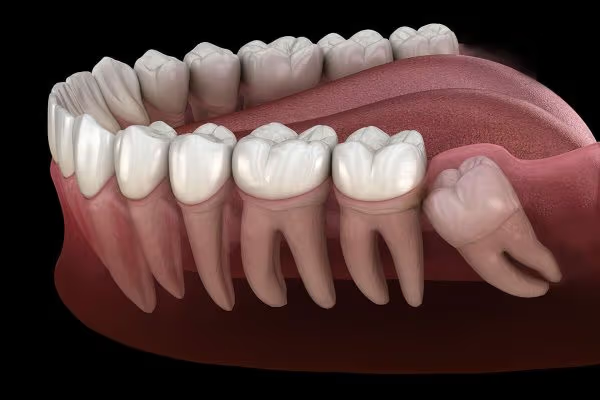

Chân răng số 8 là phần quan trọng cấu thành chiếc răng khôn – răng mọc cuối cùng trên cung hàm của mỗi người. Việc hiểu rõ

Chân răng số 7 là một bộ phận quan trọng trong hệ thống răng hàm mặt, đảm nhận vai trò thiết yếu trong việc ăn nhai và